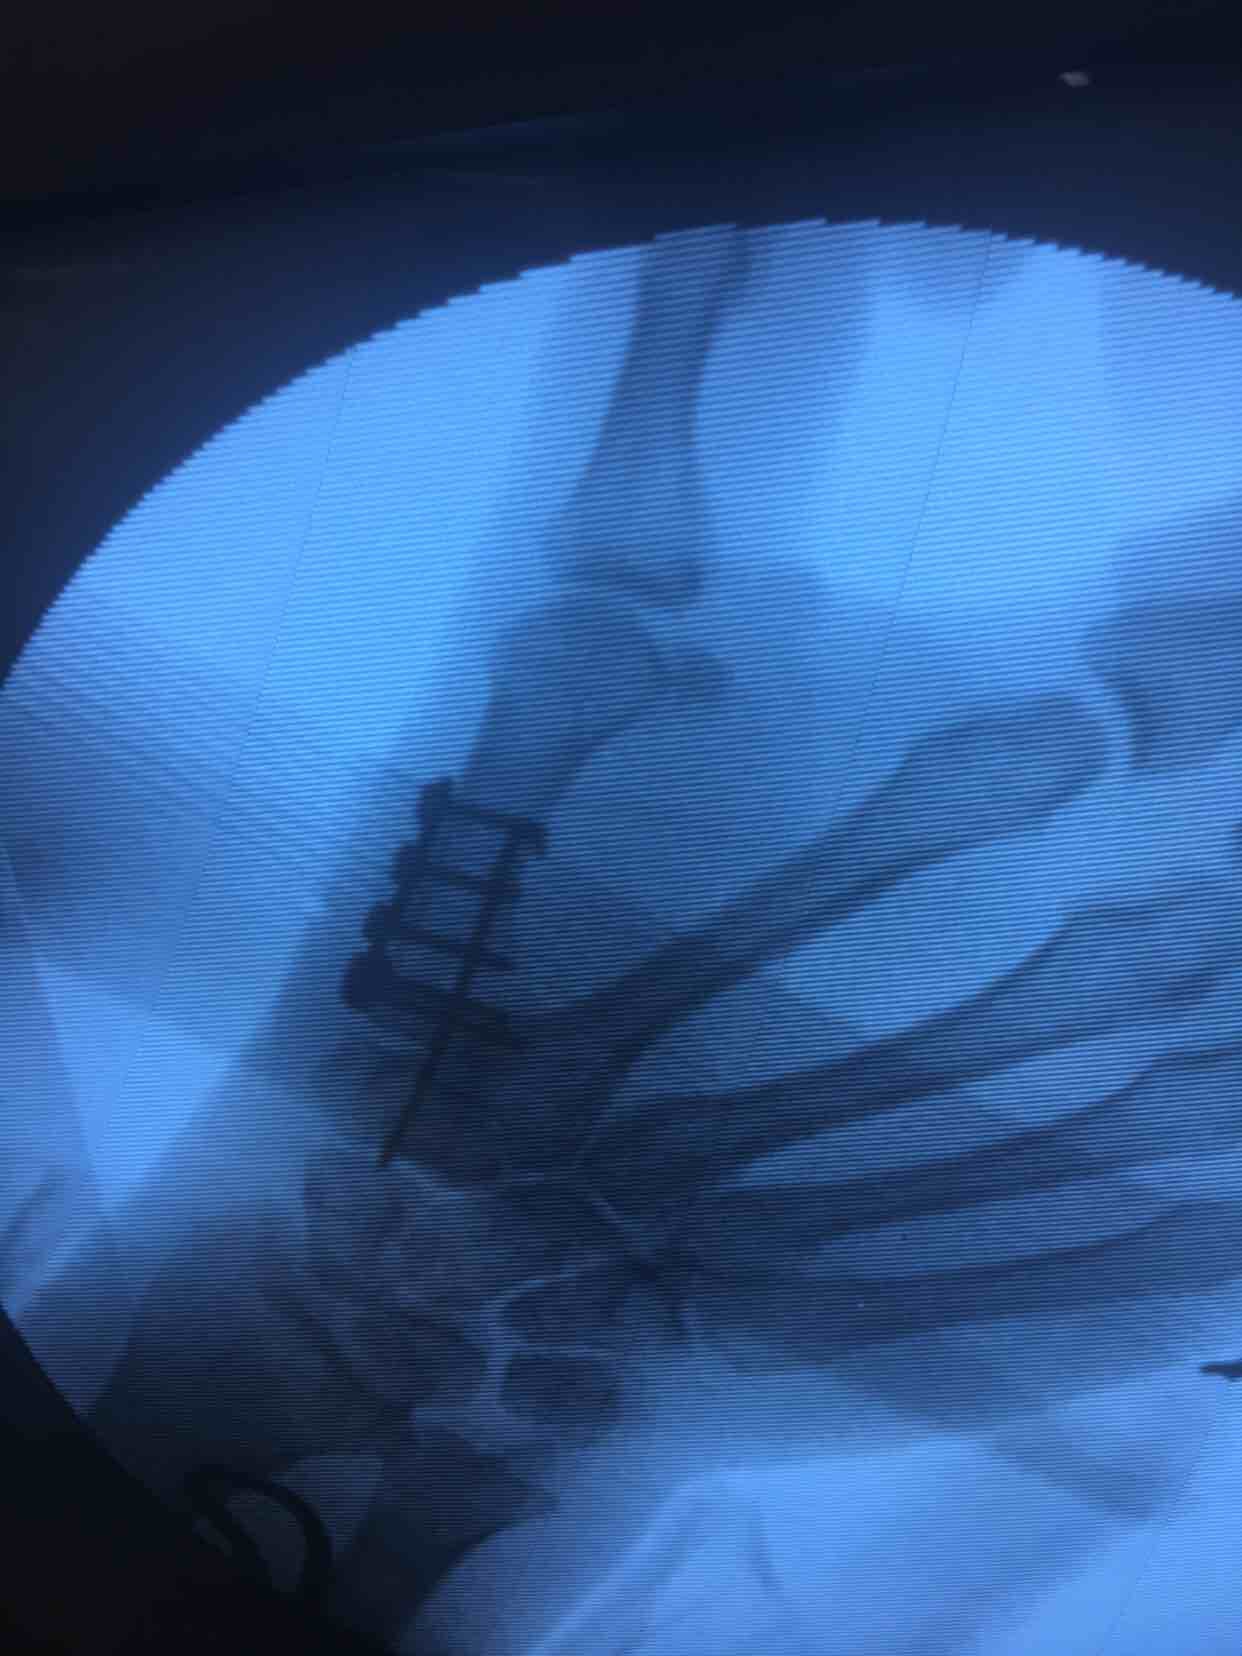

第一掌骨基底部骨折(微钢板固定)

诊断左手第一掌骨基底部骨折在臂丛麻醉下行切复内固定术,术后抗炎消肿等处理,石膏托外固定。